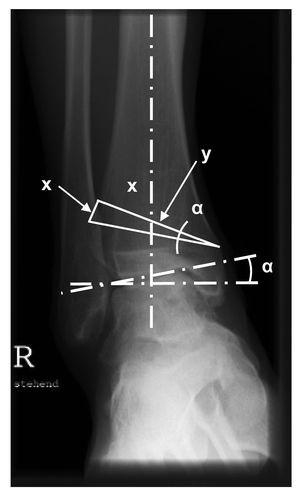

- Planificación precisa de la osteotomía considerando la ubicación de la desviación (figs. 1 y 2). La mayoría de los autores recomienda una ligera hipercorrección en valgo de 2 a 3º1,7,13,14. En el caso de desviaciones postraumáticas, se incluirán en la planificación los abordajes ya existentes.

Figura 1. Planificación de la osteotomía. La siguiente operación permite calcular aproximadamente la altura de la base de la cuña que debe extraerse de la tibia: x = y x tan a. En la osteotomía, por tanto, se realizará probablemente una corrección de 1º para una resección de 1 mm (menor en correcciones más pequeñas).